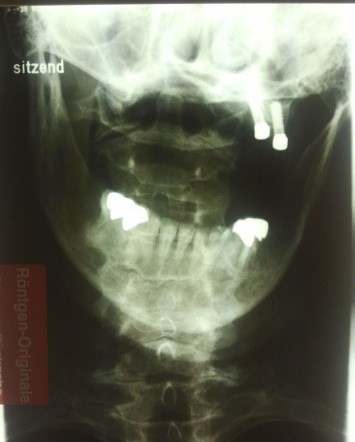

3. Badanie patologicznej czynnościowo aktywności tkankowej na kresie karkowej dolnej poprzez ucisk w okolicach przyczepów mięśni podpotylicznych (ryc. 6).